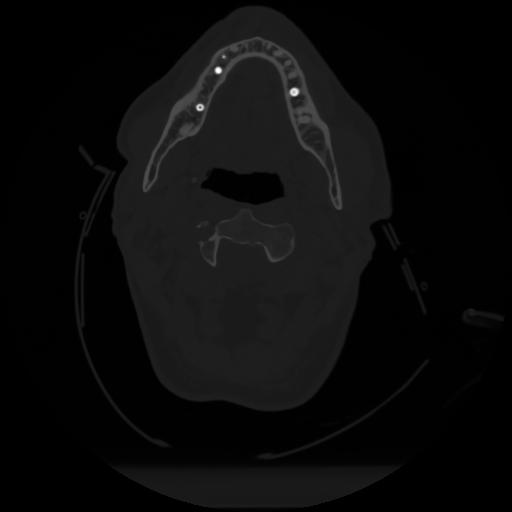

12 P.BLANDAS,,Vol,0.5,P.BLANDAS,,